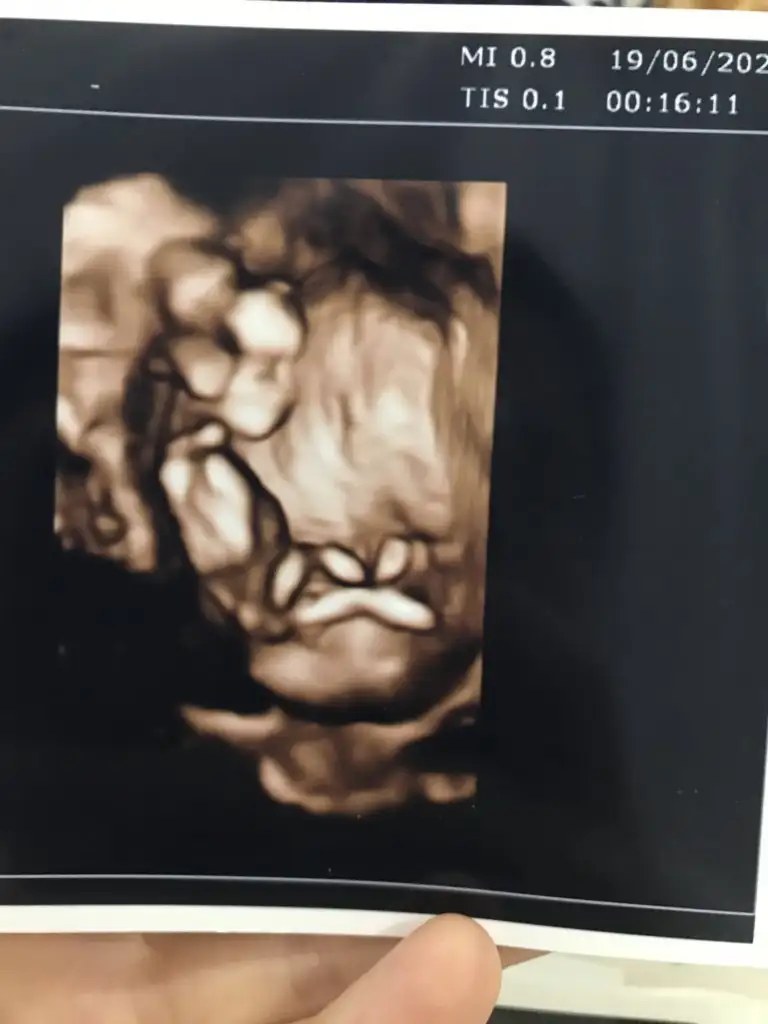

Bunlar net değilBi de bu resimler var.

Ögrendinizmi tahminim kızdışu an yanımda yok ...eve gidince bakayım o zaman..şimdiden çok teşekkürler